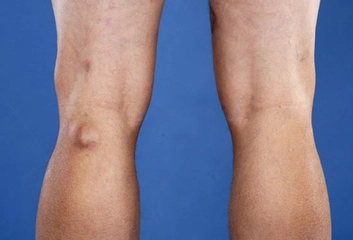

Diz kapağı ameliyatı, diz ekleminde meydana gelen çeşitli rahatsızlıkların tedavisinde uygulanan cerrahi bir müdahaledir. Bu tür ameliyatlar, genellikle diz kapağının yerinden çıkması, yaralanmalar, artrit veya diğer diz problemleri nedeniyle gerçekleştirilir. Ancak, bu tür bir cerrahinin kendi içinde belirli riskler ve sonrasında göz önünde bulundurulması gereken durumlar söz konusudur. Diz Kapağı Ameliyatının RiskleriDiz kapağı ameliyatı, her cerrahi işlemde olduğu gibi bazı riskler taşır. Bu riskler arasında şunlar yer almaktadır:

Uzun Dönem Sonuçlar ve İyileşme SüreciDiz kapağı ameliyatının uzun dönem sonuçları, hastanın genel sağlık durumu, yaş, fiziksel aktivite düzeyi ve rehabilitasyon sürecine bağlı olarak değişkenlik göstermektedir. Genellikle hastalar, ameliyat sonrası birkaç hafta içerisinde günlük aktivitelerine dönebilir. Ancak, tam iyileşme süreci birkaç ay sürebilir. SonuçDiz kapağı ameliyatı, birçok hastada yaşam kalitesini artırma potansiyeline sahip önemli bir cerrahi müdahaledir. Ancak, yaşanabilecek riskler ve ameliyat sonrası bakım süreci göz önünde bulundurulmalıdır. Hastaların, cerrahiden önce ve sonra doktorlarıyla düzenli iletişimde kalarak en iyi sonuçları elde etmeleri hedeflenmelidir. |